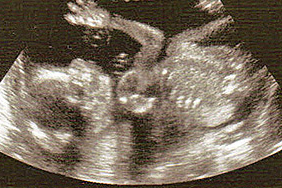

Депутат предлагает наделить эмбрионы человеческими правами

Виталий Милонов готовит проект, по которому эмбриону будет присвоен статус гражданина, и как следствие, введен запрет на аборты.

Депутат Законодательного собрания Петербурга считает, что нельзя использовать понятие «эмбрион». Ведь это такой же член общества, как и люди, которые, например, находятся в коме. Аборт – это не косметическая операция.

Депутат предлагает считать эмбрион гражданином с момента биения сердца.

Источник фото: sochi.bezformata.ru